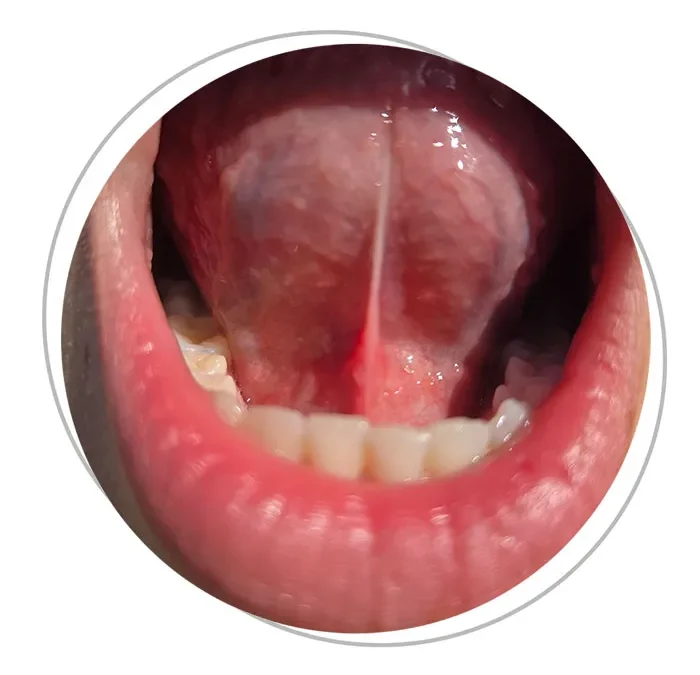

Una delle cause più comuni di deglutizione atipica è la presenza di un frenulo linguale corto, cioè una limitazione anatomica del sottile legamento che collega la lingua al pavimento della bocca. Questo impedimento ostacola il corretto posizionamento della lingua contro il palato durante la deglutizione e la respirazione, costringendo l’organismo ad adottare compensi muscolari e posturali nel tempo.

Nei casi in cui il frenulo linguale rappresenti un impedimento funzionale, viene valutata la possibilità di una frenulectomia, ovvero la rimozione chirurgica del frenulo. In questo contesto entrano in gioco figure fondamentali come il logopedista e il chirurgo orale, che lavorano in stretta collaborazione con il team odontoiatrico per garantire un intervento mirato e ben integrato nel percorso riabilitativo.